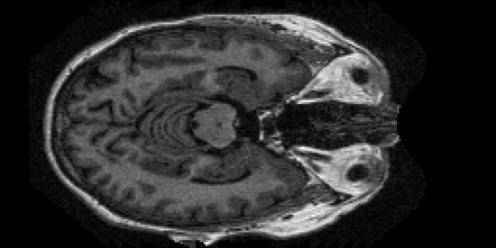

(b) Moderate dementia MRI sample.

Refer to caption

(c) Mild dementia MRI sample.

(d) Very mild dementia MRI sample.

Figure 2: Representative brain MRI examples from the OASIS-1 dataset corresponding to the four Alzheimer’s disease categories considered in this study.